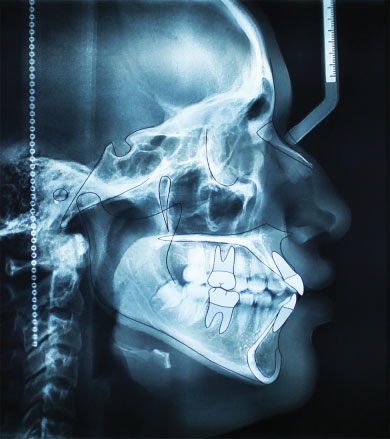

Las cefalometrías o trazados cefalométricos se emplean para los estudios y planificaciones de tratamientos de ortodoncia. Tienen como objetivo obtener medidas del cráneo y compararlas con patrones estándar evaluando y analizando la relación entre los huesos del cráneo, la mandíbula y los dientes, así como el crecimiento facial y las anomalías esqueléticas.

No se han observado diferencias importantes entre el trazado cefalométrico digital (fig.1) y el manual (fig. 2), así mismo, no se han presentado diferencias significativas entre la cefalometría en 2D (fig. 3) y la cefalometría en 3D (fig.4a, b, c).

Particularmente los ortodoncistas y maxilofaciales pueden confiar plenamente entre los datos aportados por la cefalometría en 2D y los aportados por la cefalometría en 3D excepto a los datos aportados en la inclinación del ICI (incisivo central inferior).